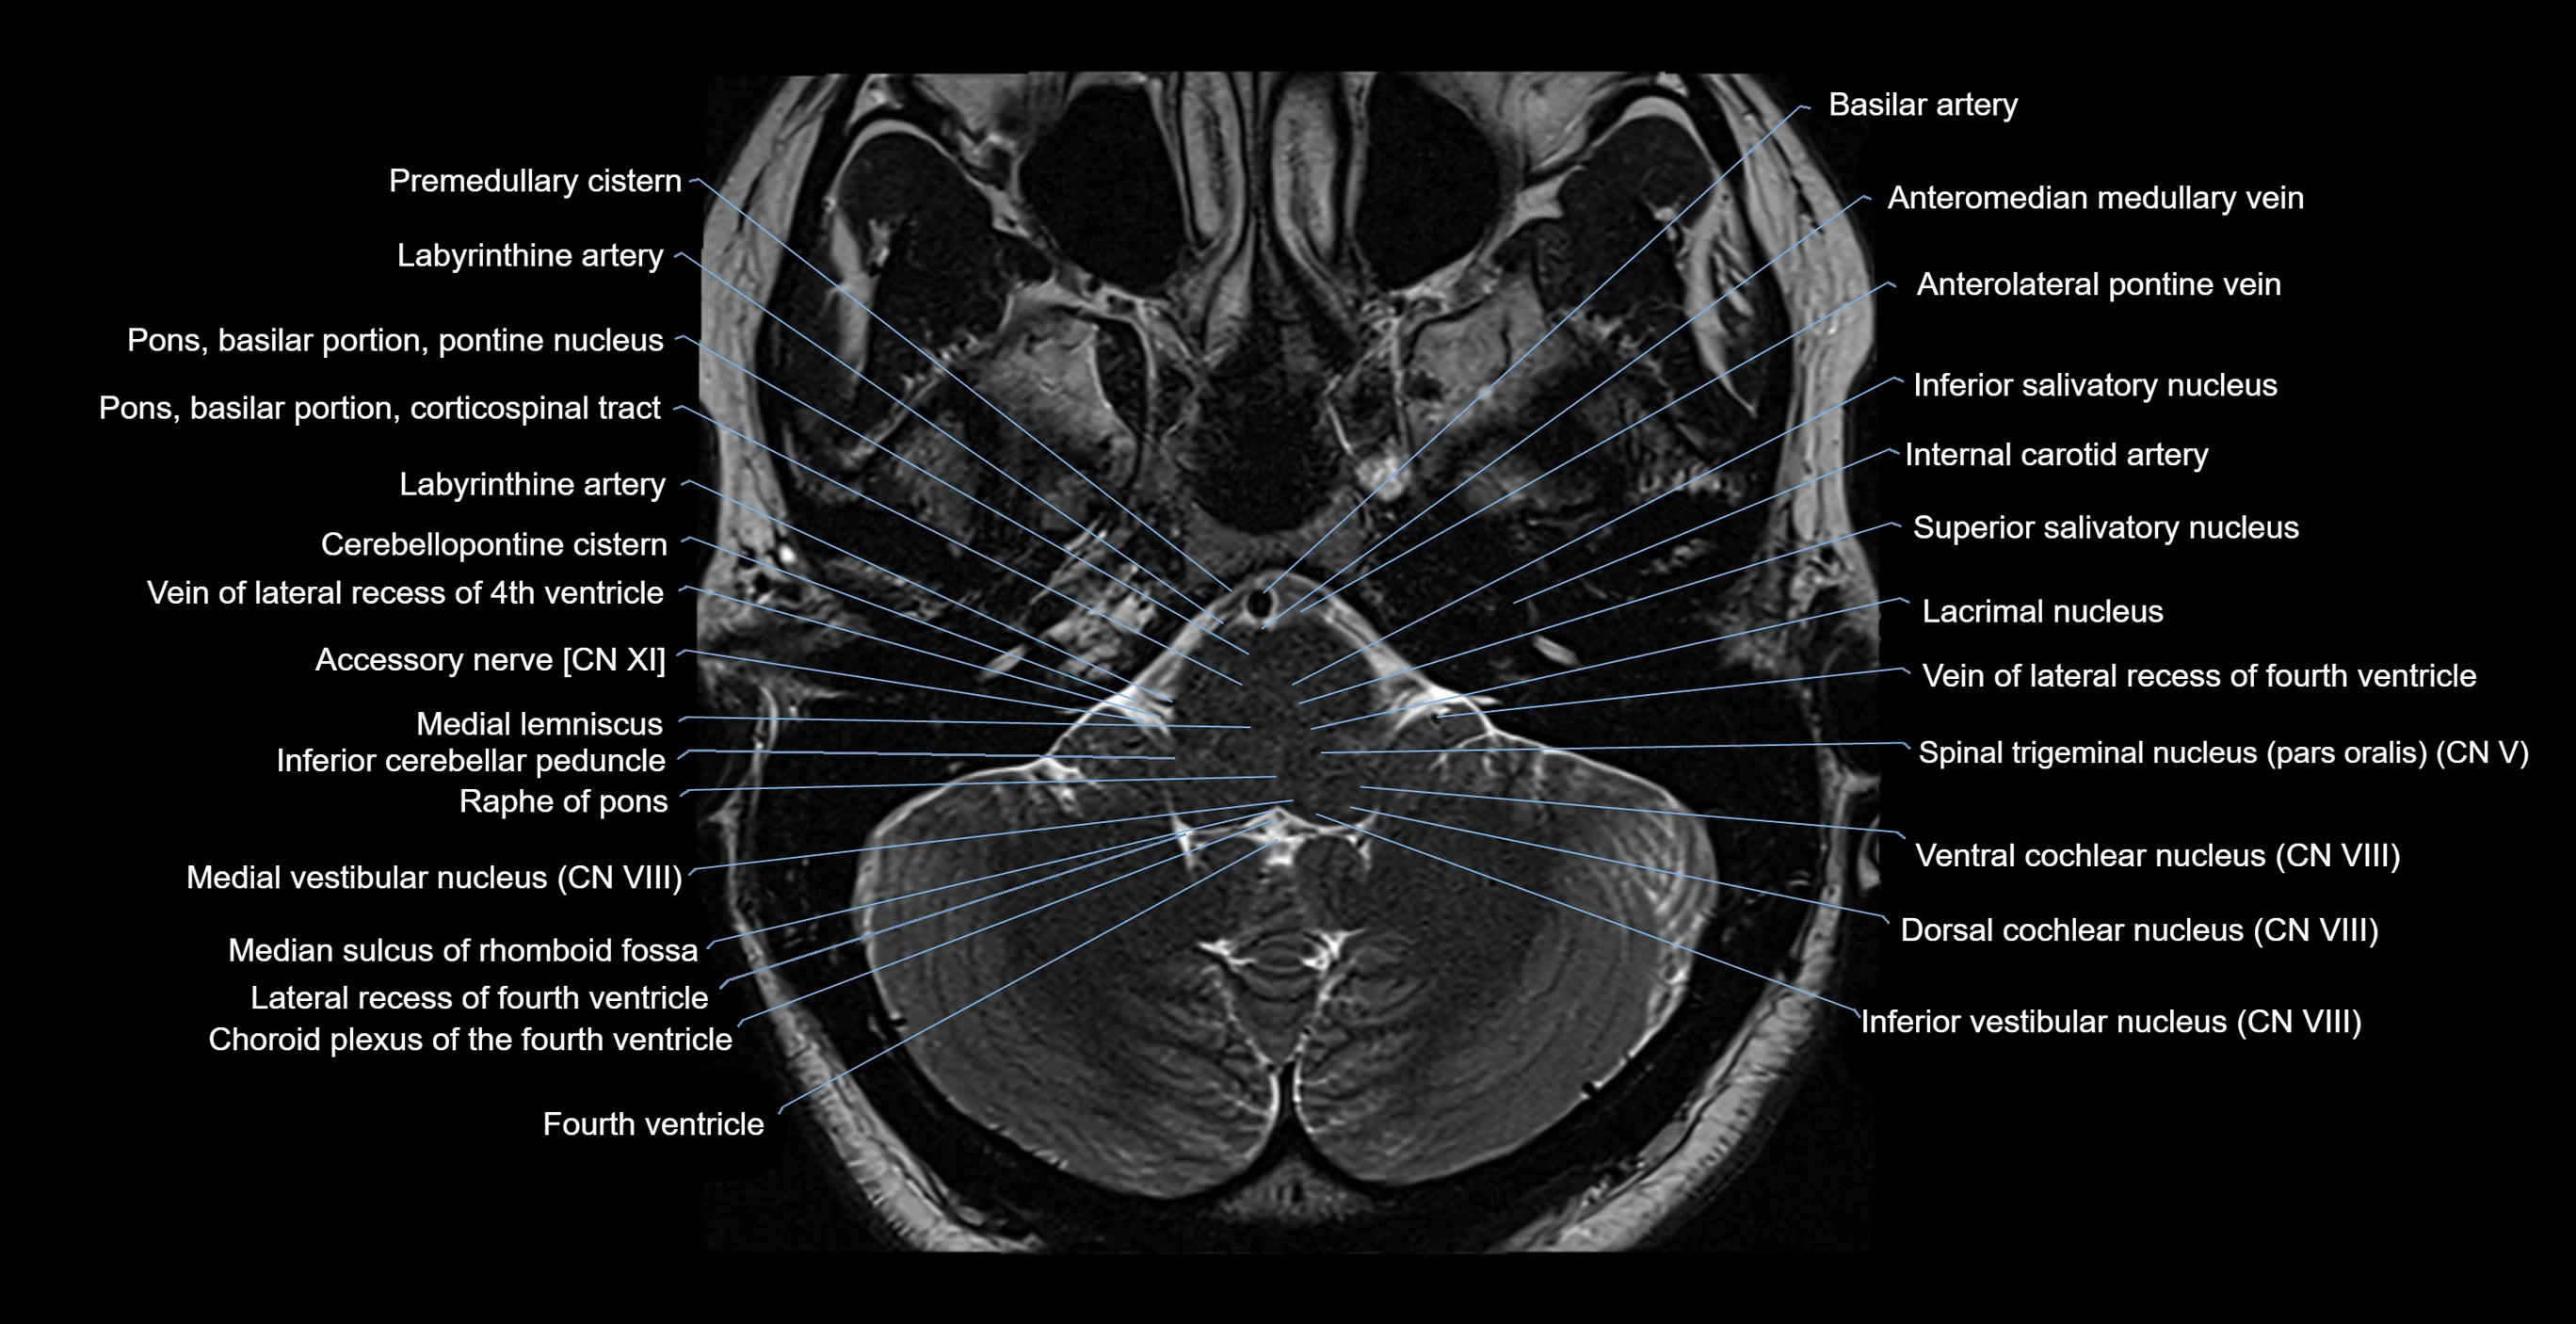

MRI images